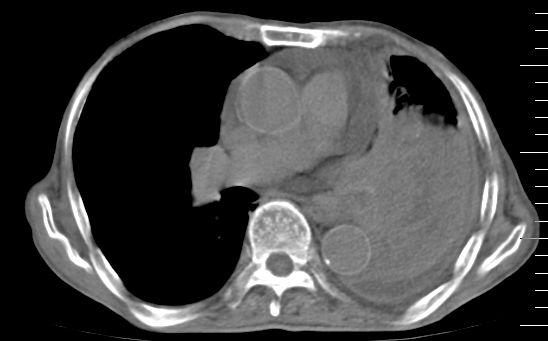

标题: CT10141:男、84岁,咳嗽、咯血1年。 [打印本页]

标题: CT10141:男、84岁,咳嗽、咯血1年。

支持左侧中央型肺癌伴下叶肺不张\\纵隔淋巴结转移.左侧包裹性胸腔积液\\心包积液.左侧少量胸腔积液..慢性支气管炎伴部分间质纤维化.

支持:左侧中央型肺癌伴下叶肺不张\\纵隔淋巴结转移.左侧包裹性胸腔积液\\心包积液.左侧少量胸腔积液..慢性支气管炎伴部分间质纤维化.另:支气管分支根部明显阻塞 狭窄,内膜凸凹不平,提示内膜增生物。

咯血病史较长,左肺下叶实变,体积未明显缩小,隐约可见血管影及坏死阴影,双肺门及纵隔淋巴结增大,心包增厚积液,纵隔右移位,单侧胸腔积液,首先考虑:大叶型肺泡癌伴纵隔心包转移。